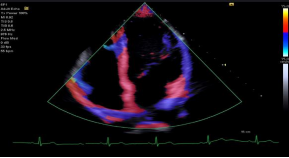

Doppler Tissue Imaging (DTI) 组织多普勒:

‒ DTI 提供了组织平均速度的实时成像显示,在采样区域内的用户选择感兴趣的使用不同的用户选择颜色编码地图

‒ 适用于 5P1, 8V4, 10V4, 11M3等探头